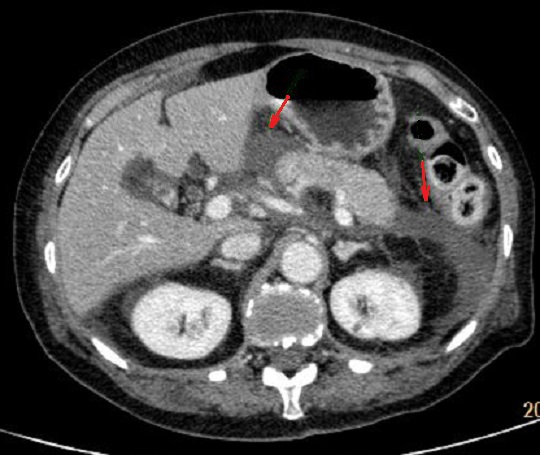

Image radiologique TDM de pancreatite

necrotique hemorragique est : Image de presente des

foyers collectiones necrosants intra ou extra

pancreatique absence ou defaut de rehaussement apres

injection de contrast intraveineuse . Les collections de

l'affection sont compose de necrose , d'hemorragie et

exudative . La formation des abces peut en visible des foyer

de collective hydrique . Image de reactionelle ganglionaire

,epanchement ascitique ou epanchment pleurale peut se en

visible

Image radiologique de

pancreatite forme necrotique hemorrhagique avec

aspect des foyer de necrose parenchymateuse

hypodense et defaut de rehaussement ( fleche rouge )

. Image radiologique TDM phase veineuse |

|

Image radiologique TDM

arteriel phase d'une pancreatite necrosant

hemoragique : Pancreas en volumineuse , presence des

foyers de necrose , hemorragique et exudative a

hypodense ,absence ou moindre de rehaussement situe

intra et extra pancreatique |